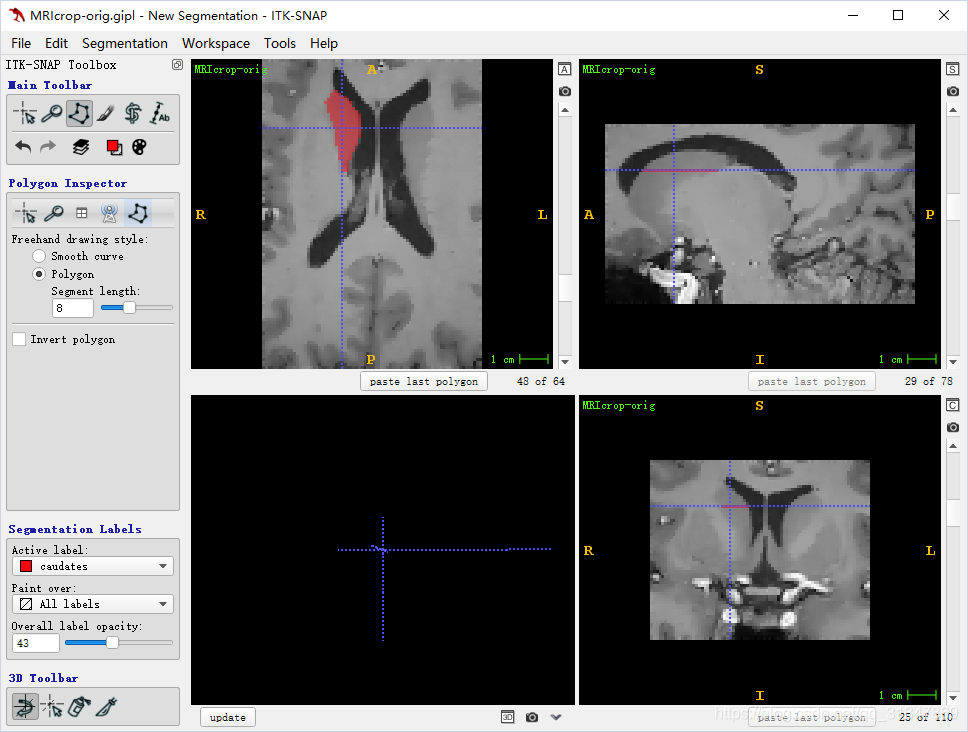

使用界面

左下方视图显示了当前的 3D 视角,其余三个视图是三个正交的切片图(轴向,冠,矢)

四块视图窗口下的蓝色按钮用来单独对当前视图进行一些操作

左边是控制面板

顶部的 menu 用于加载和保存图像,以及一些基本设置

其余按键会根据当前操作的模式出现/消失

三个切片窗口分别显示了:

- 轴向面

- 冠状面

- 矢状面

右侧有一个滚动条,滚动条下方是切片计数器,左边的数字是当前的切片索引,右边的数字是该方向上的切片总数

手动分割:

在 Active Label 下选择一个标签,然后基于此标签进行分割

Paint over 为 all labels,表示分配的标签将覆盖掉已经有标签的 voxels

选择 Polygon mode,左键单击绘制边界,注意最后一条关闭多边形的线会自动出现

视图下方可以 undo 或 clear 绘制的标签

分割好以后视图下方会变成:

此时在视图上手拉一个矩形框,可以选中所有分割的结点,拖动矩形框就可以移动分割的边框:

单独拖动某一个结点,也可以修正分割结果

修改好之后,点击 accept,多边形内会填充当前标签的颜色

注:记得将 Overall label opacity 调大一点,不然看不到标签

要清除标签的某一部分,可以将当前标签设置为 “Clear”,覆盖掉需要清除的标签即可。

SNAP 可以保存最近依次绘制的多边形,当在同一视图的不同切片上切换时,可以直接用 paste 复制多边形区域,然后做出微调即可。

在一个视图中绘制的多边形,在其他两个视图中表示为一条线。

在三个视图中都绘制好多边形区域,点击 3D 视图下的 update,就可以看到 3D 分割结构: